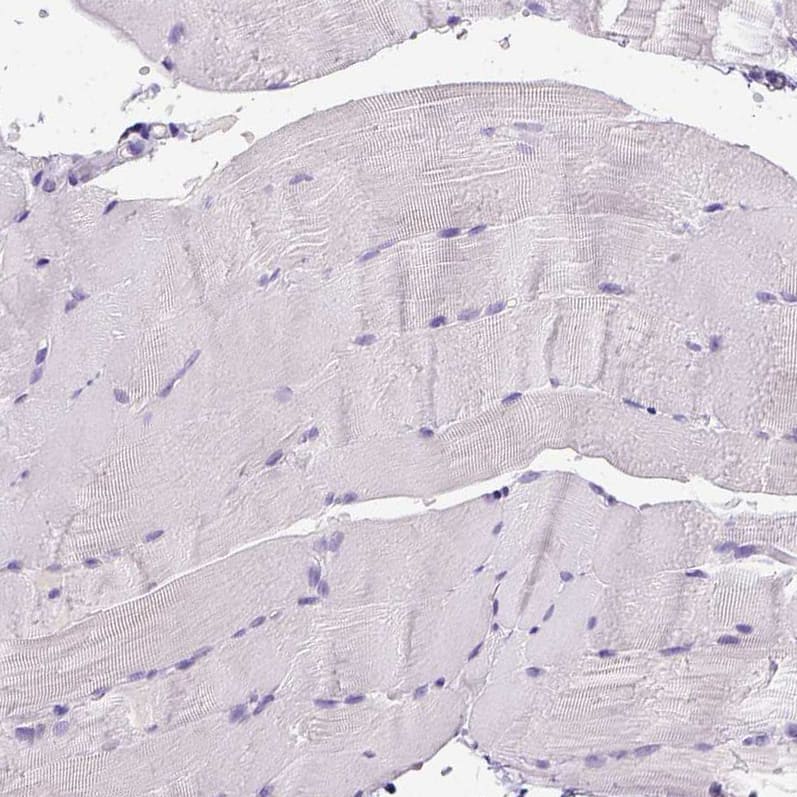

Staining of human skeletal muscle shows no positivity in striated muscle fibers as expected.